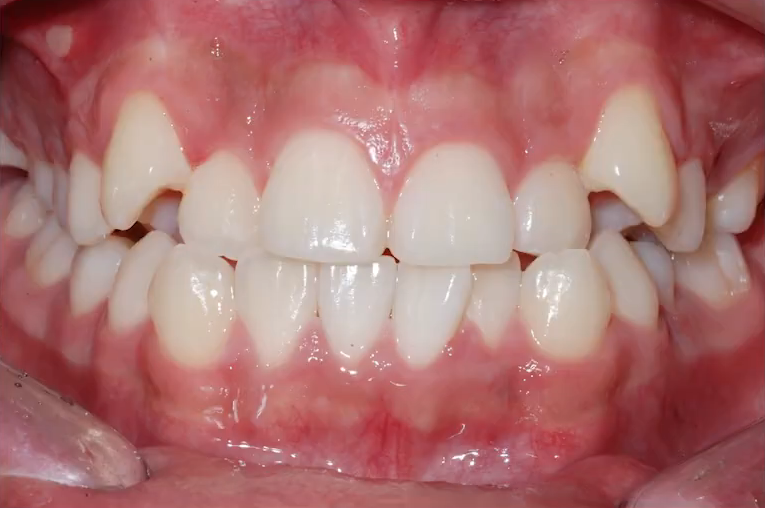

악 궁 확 장 장치로 비발치 교정한 사례를 하나 가지고 와봤는데요.

앞니가 많이 삐뚤빼뚤합니다.

치아가 가지런히 배열될 공간이 부족하니, 덧니가 나와있는 상태고요.

타 치과에서는 발치 후 교정을 권유받았지만

아직 성장기가 남아있는 청소년 환자다 보니 가능한한 비발치 교정으로 진행하기로 했는데요.